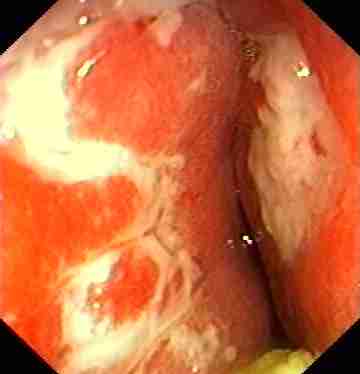

Oesophagus:

Web or ring due to chronic reflux diseases